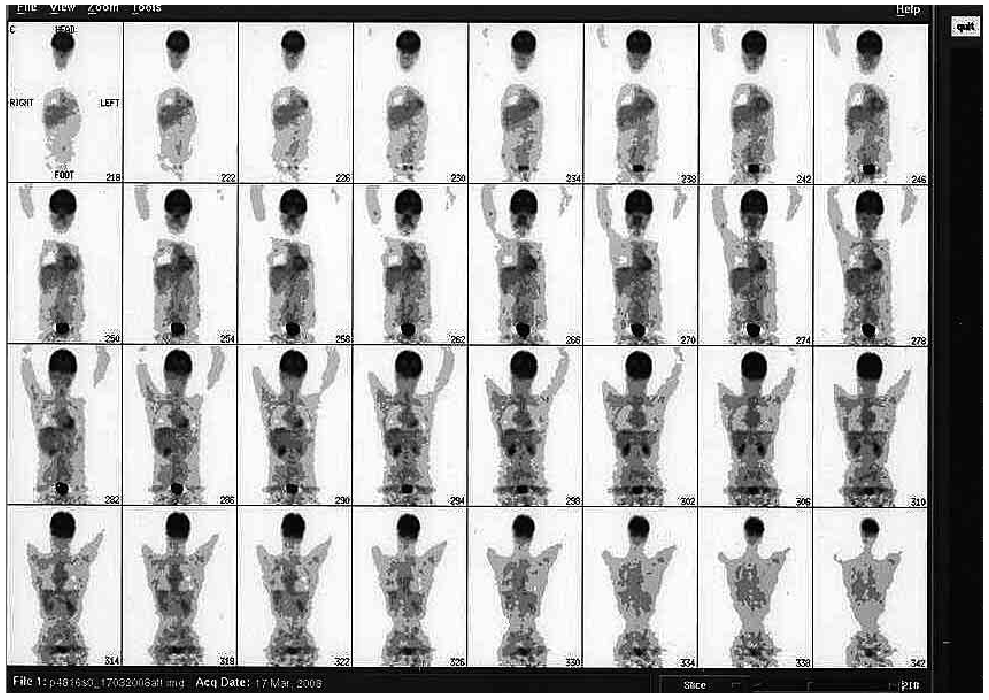

Complete objective response of neuroblastoma to biological treatment.

Figure10-11-12-...